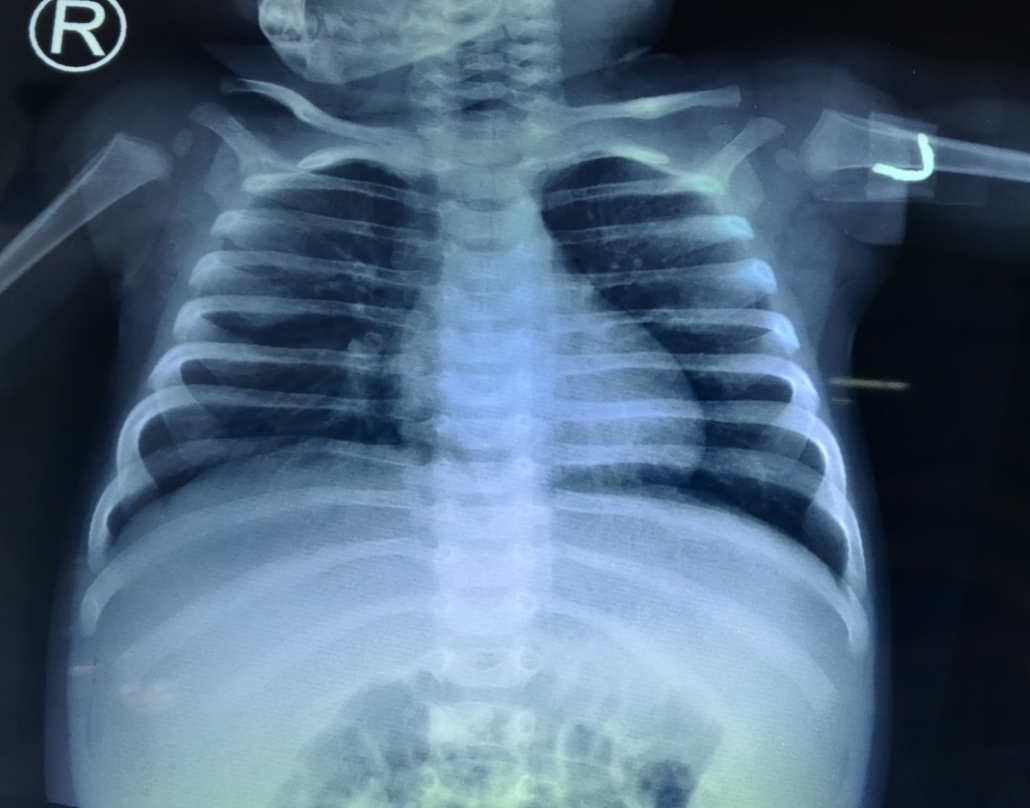

In view of pneumonia, anemia, hepatomegaly, splenomegaly, icthyosis vulgaris and axillary lymphadenitis, disseminated tuberculosis was suspected and worked up. Mantoux test showed induration with size of 20 mm (Figure 2), ESR was 124 mm/hr. Gene Xpert of nasopharyngeal aspirate was negative, AFB staining of nasopharyngeal aspirate was negative. Fine needle aspiration cytology from the lymph node revealed positive AFB on staining (Figure 3). Considering possibility of disseminated tuberculosis, the child was started on ATT. The symptoms were settling for 1-2 days and then recurring, with high total leucocyte count and very high CRP for the first one month of ATT.

Figure 3 Demonstration of AFB in FNAC of lymph node.